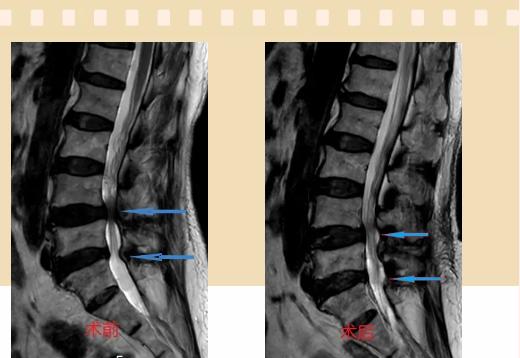

入院后李鵬副主任醫(yī)師為其進行了詳細的查體,完善了術前的檢查,明確診斷為:腰椎管狹窄癥(L4/5、L5/S1),病人合并2型糖尿病,請內分泌科會診,穩(wěn)定血糖后,麻醉科會診病人,排除手術禁忌,李鵬為病人制定了手術方案:單側入路雙側減壓(ULBD)。

手術采用三個微創(chuàng)小切口,兩個節(jié)段減壓手術時間2.5小時,出血50ml。術后2天腰圍保護下床活動,術后5天順利出院。

傳統(tǒng)腰椎管狹窄癥的手術治療,往往需要切開減壓,同時需要內固定融合術,創(chuàng)傷很大,同時可能需要輸血,臥床時間較長,病人合并糖尿病,感染風險也高,而本次采用的UBE-ULBD手術切口更小(加起來約3cm,如果是單節(jié)段狹窄只需要不到2cm切口)、創(chuàng)傷更小,術后恢復較快,可以更早地恢復正常活動。

此外,手術保留了病變節(jié)段的穩(wěn)定性,是一種微創(chuàng)的椎管減壓手術,能通過切除部分椎板、關節(jié)突關節(jié)、黃韌帶來解除神經(jīng)根和硬膜囊的壓迫,不需要額外行腰椎內固定術,不需要螺釘及融合器的植入,病人術后腰椎的活動度不受影響。(盧   闖  劉   旭   袁錦鈺)